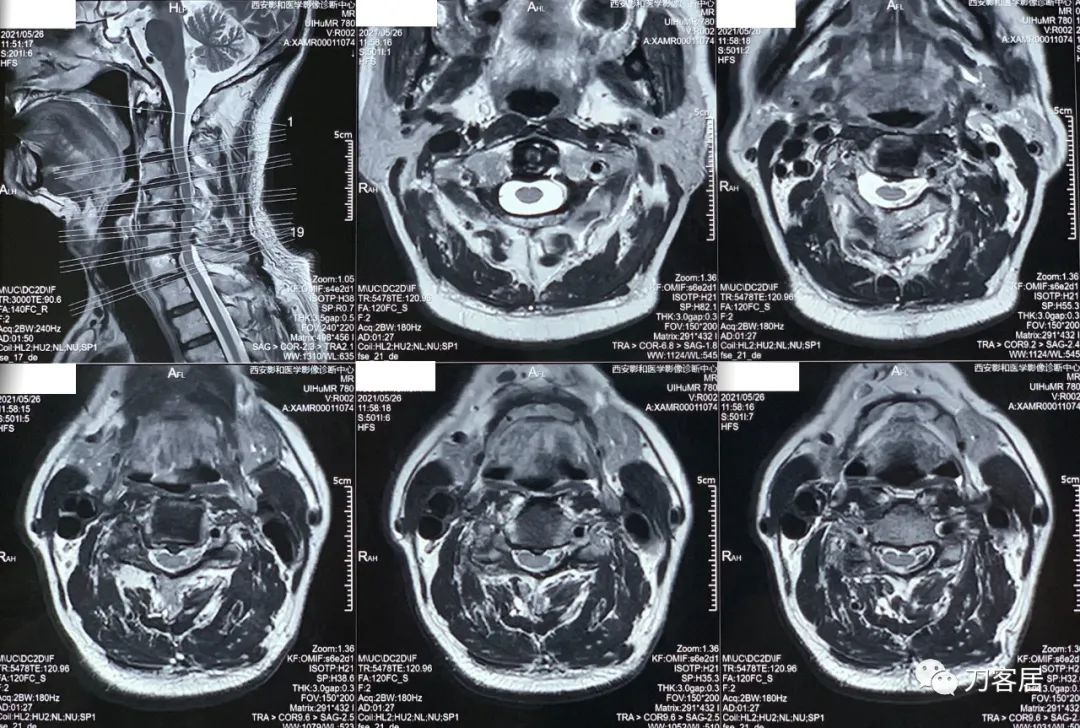

辅助检查: 自带颈椎MRI,提示颈椎轻度后凸畸形,颈3-4,颈4-5,颈5-6,颈6-7椎间盘突出,椎管狭窄。骨密度提示骨量减少。

20210526-颈椎MRI T2相,显示颈3-7轻度后凸,椎间盘突出,椎管狭窄,脊髓受压。

20210526-颈椎MRI T1相,显示颈3-7轻度后凸,椎间盘突出,椎管狭窄,脊髓受压。

20210526-颈椎MRI经椎间盘横截面扫描。